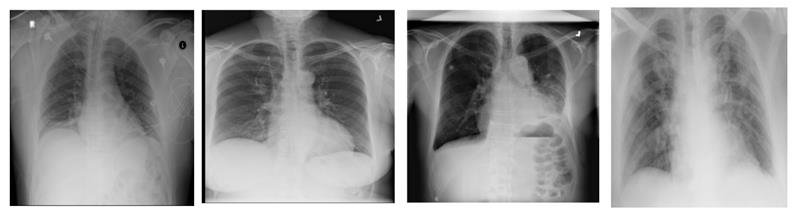

Figure 11

Heatmap of X-ray images with (from left-to-right) Edema, Effusion, Emphysema, COVID findings.